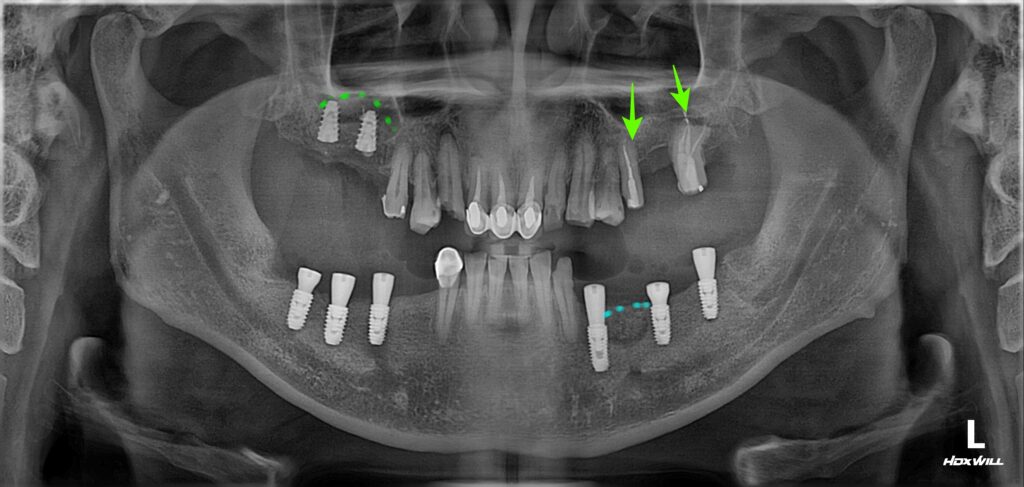

이렇게 복합적으로 치료해야 하는 경우 가장 먼저 해야 할 일은 임플란트 식립입니다.

신경치료나 크라운 보철 치료의 경우 기간이 그리 오래 걸리지 않지만 임플란트의 경우 임플란트와 뼈가 붙는데 시간이 수개월 소요되기 때문이죠.

위와 같이 임플란트를 심고 뼈가 붙는 시간을 3개월 기다렸습니다.

상악동 거상술과 (연두색 점선) 뼈이식(하늘색 점선)을 동반하여 임플란트를 식립하였고

임플란트가 붙는 기간 동안에 어금니 신경치료까지 진행하였습니다.

임플란트 식립 후 3개월 뒤에 임플란트와 뼈가 단단하게 붙은 것을 확인한 뒤 본을 떠서 임시치아를 만들었습니다.